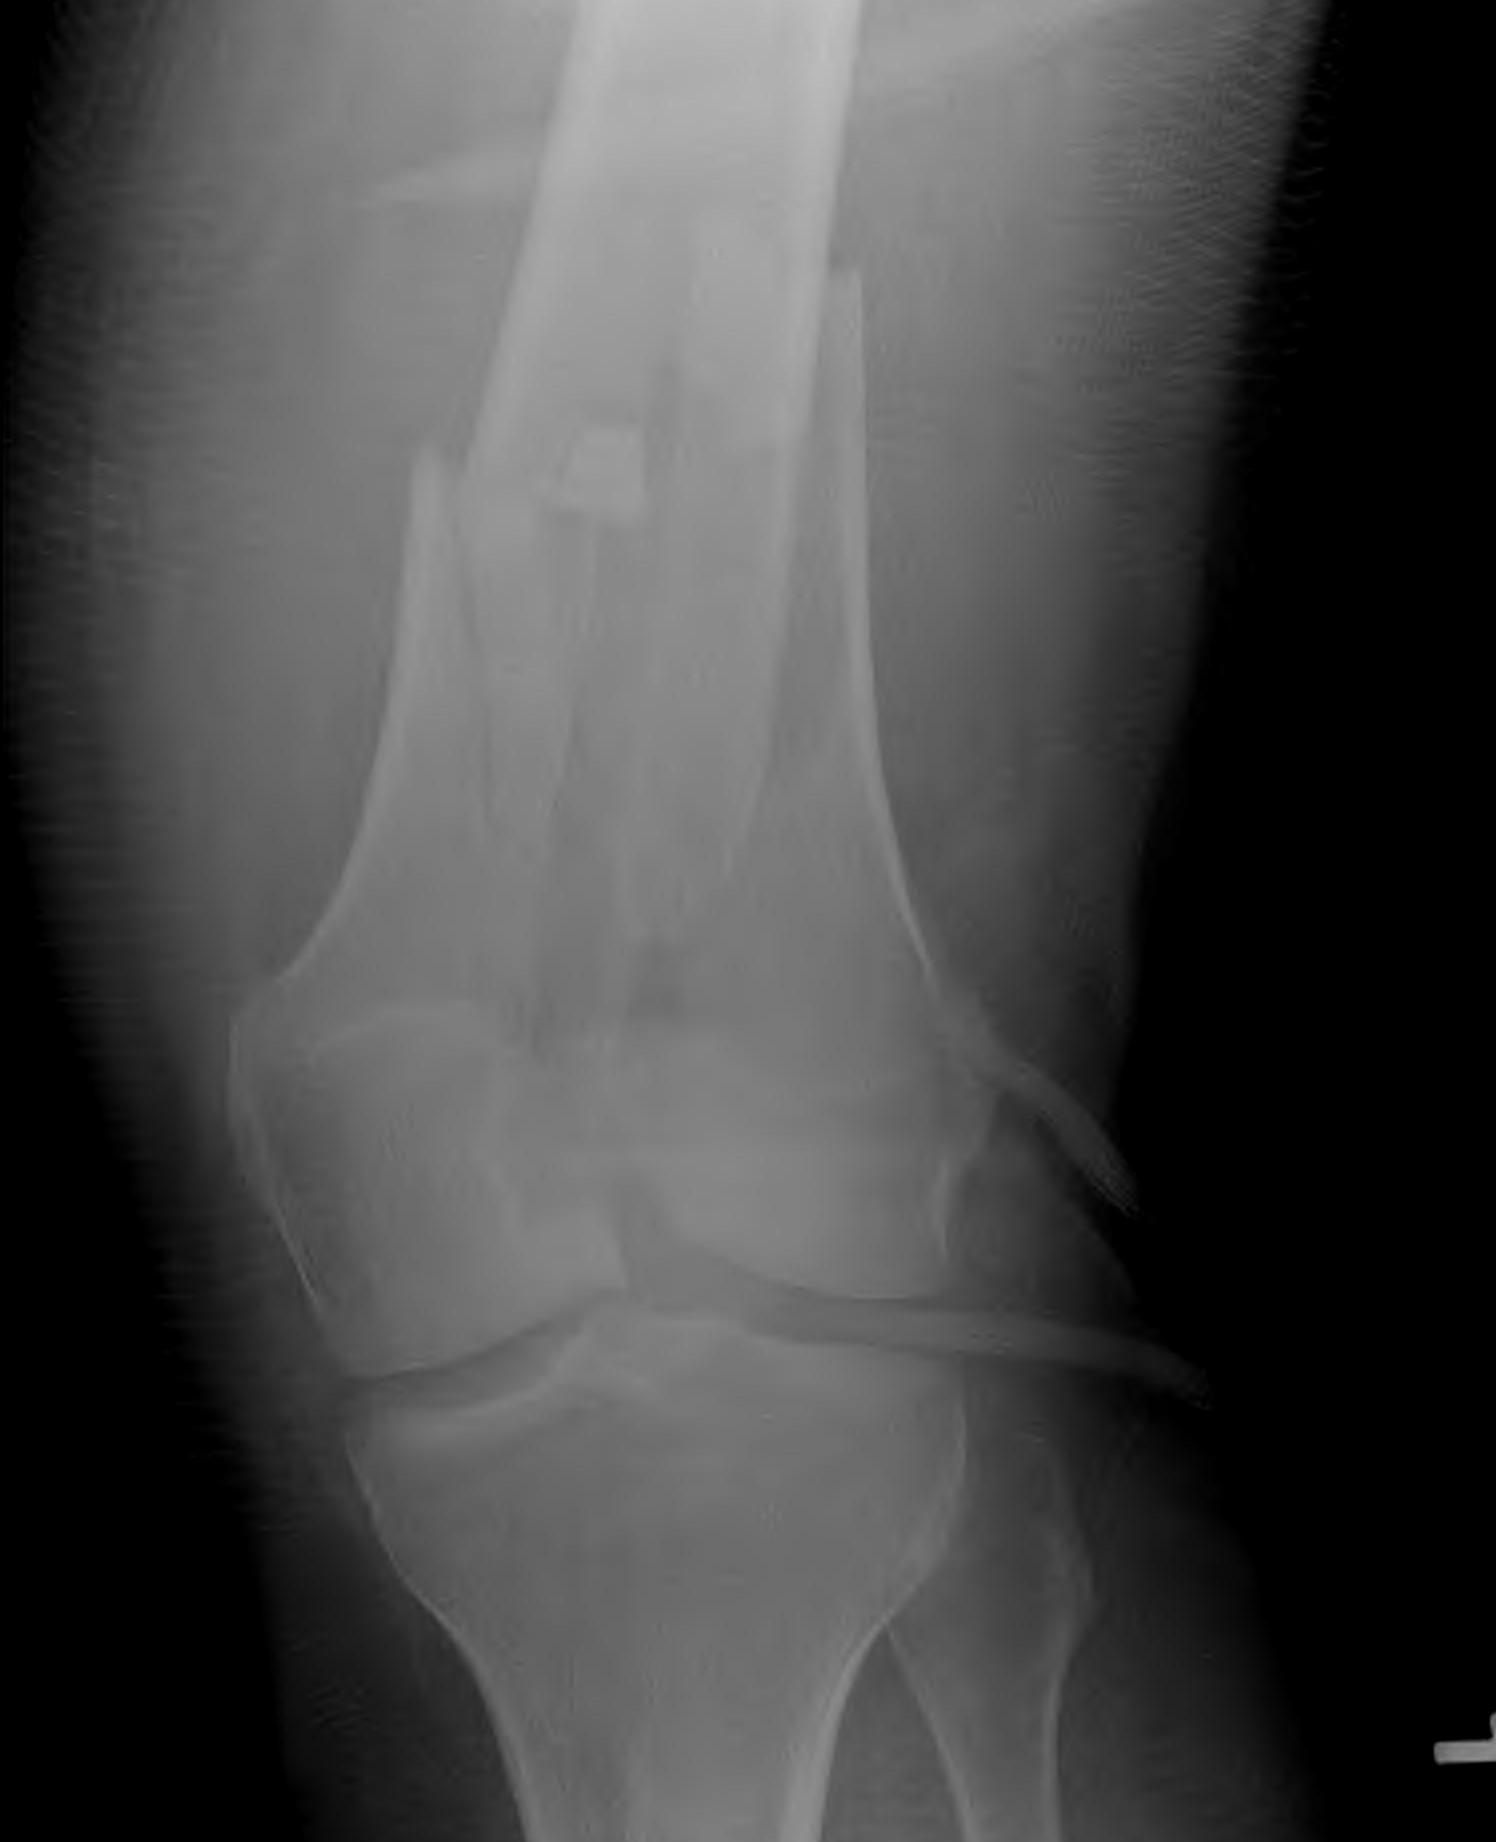

AO Type A: Supracondylar / Extra-condylar

Xray

Options

Lateral plate

Retrograde IM nail